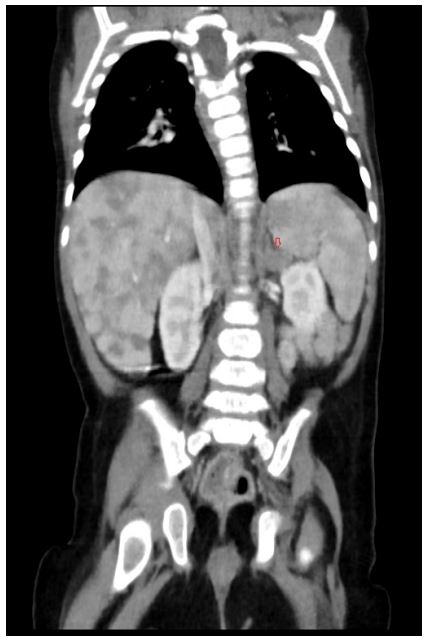

Abdominal sonography (Fig. 1) confirmed hepatomegaly (10,6cm) and numerous nodular formations suggestive of metastatic lesions, the largest measuring 21mm. No other ultrasound abnormalities were detected, namely space-occupying lesions in the adrenal gland areas or along the paravertebral space. Chest radiography was normal.

Thoracoabdominal computed tomography (CT) (Fig. 3) showed an enlarged left adrenal gland (15mm), along with the previously identified hepatic lesions, suggesting a primary tumour arising from the left adrenal gland with secondary liver metastasis. Bone marrow aspirate and biopsy (performed for staging) showed no abnormalities.